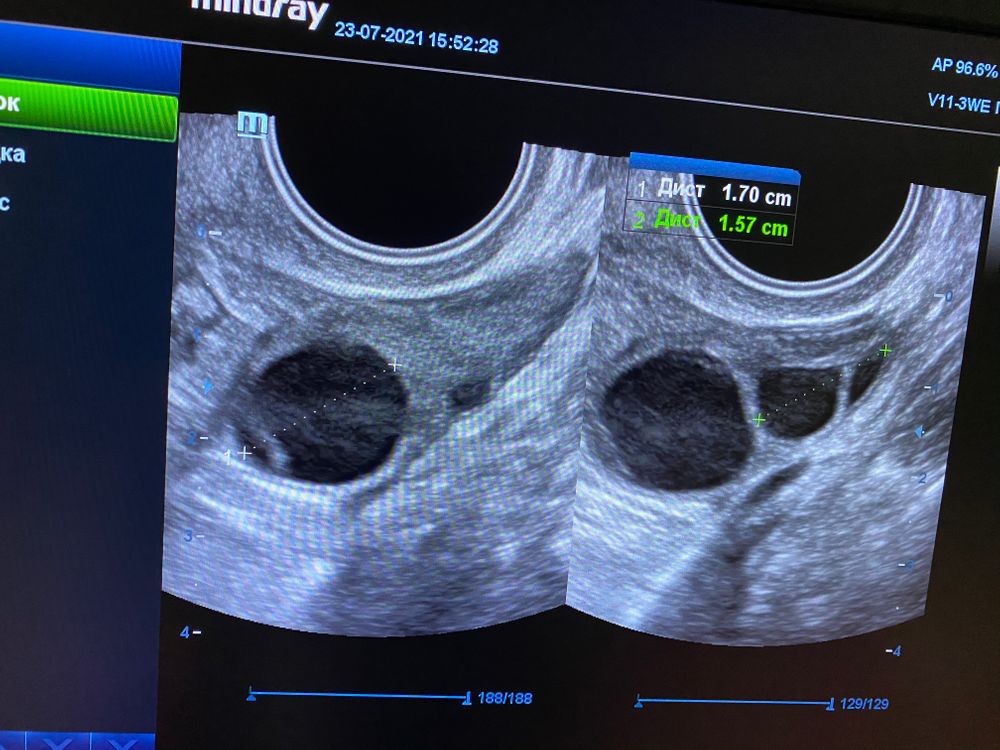

Сегодня 10 дц сделала ужасное узи, врач сначала сказала что овуляция уже прошла, после моих слов что всего 2 дня назад фолликулы были 13 мм, она чудесным образом все таки нашла 2 дф 🤦🏻♀️ созванивалась с каким то врачем и скидывала ей фотки, правильно ли она указывает🤦🏻♀️

Итак, если она верно замерила, то фолликулы сегодня 17,7. Растут они примерно по 2 мм в день, а мне назначили ещё одно узи на пн. И у меня назрел вопрос, а доживут ли эти фолликулы до узи пн и инсеминации вторника? Как считаете?

эндоментрий нарос до 9 мм ( если его кончено же верно замерили)